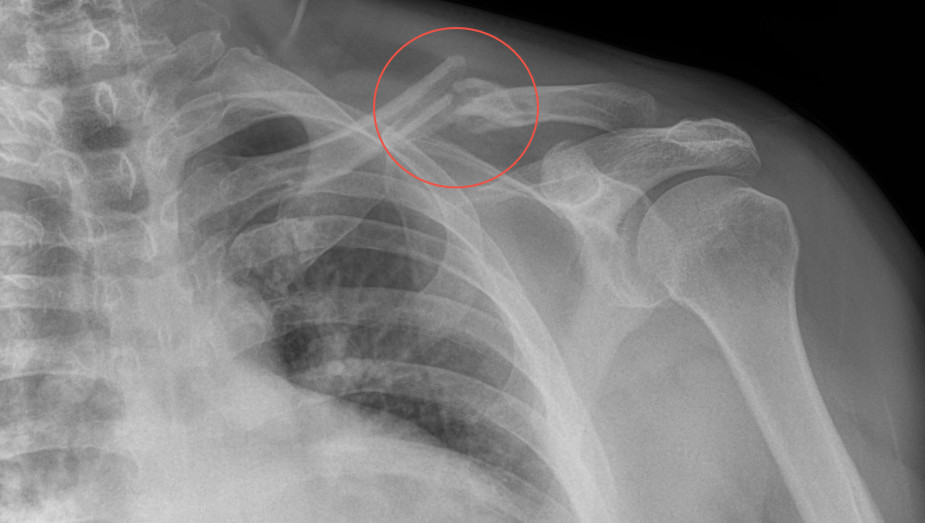

Radiología Digital como Herramienta Complementaria en el Dictamen de Bienes Muebles

Desde el descubrimiento de los rayos “X” y las placas radiográficas por Wilhelm Conrad Roentgen y su posterior difusión a través de la Asociación Físico médica de Wurzburg el 28 de diciembre de 1895, que fue la primera asociación que habló de los nuevos rayos que podían penetrar el cuerpo y fotografiar los huesos, ha habido muchos cambios tanto en la forma de obtener, procesar e incluso en la forma de visualizar, manejar y almacenar las placas radiográficas.